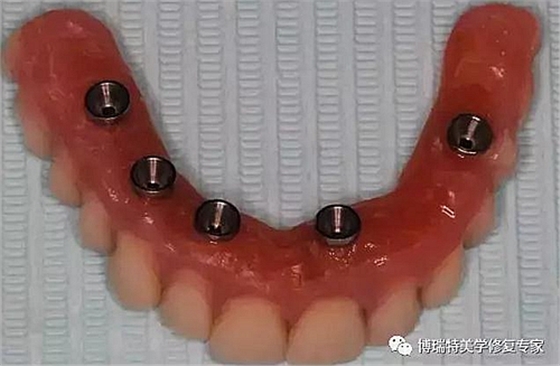

5、尤其適合全口無牙頜的種植方案;

按照調(diào)整修復(fù)螺絲方向,可以分為螺絲固位直基臺與螺絲固位角度基臺,螺絲固位角度基臺有17°和30°兩種。兩種角度基臺均有抗旋結(jié)構(gòu)設(shè)計(jì)。

按照穿齦高度,螺絲固位直基臺有三種穿齦高度:分別為1mm、2mm、3mm。

螺絲固位17°角度基臺有三種穿齦高度,分別為1-2.5、2-3.5和3-4.5mm。

螺絲固位30°角度基臺有三種種穿齦高度,分別為1-3.5、2-4.5和5-5.5mm。

可以根據(jù)不同的傾斜種植體調(diào)整修復(fù)角度。